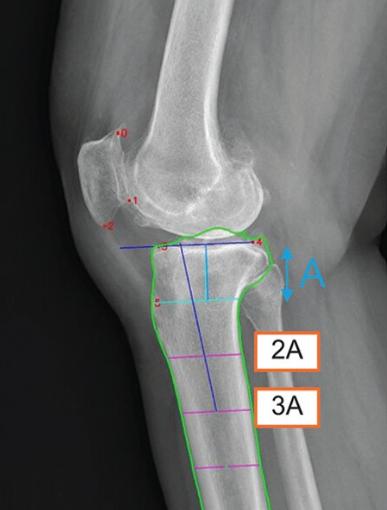

노두현 서울대병원 정형외과 교수(김성은 연구교수)와 미국 미네소타대, 노르웨이 베르겐대 공동연구팀은 2009~2019년에 촬영된 1만여건의 무릎관절 측면 X-레이 영상을 바탕으로, 경골 후방 경사각을 빠르고 신뢰성 있게 측정 가능한 딥러닝 모델을 개발했다고 26일 발표했다. 6개의 해부학적 기준점(빨간 점)을 자동 인식한 후, 경골의 관절선과 중심축(파란 선)을 결정해 경골 후방 기울기를 계산한다.

이 모델은 무릎뼈의 6개의 해부학적 기준점(랜드마크: 슬개골 상·하단 극, 슬개골 관절면 원위부 가장자리, 내측 경골 고원 전·후방 정점, 경골 결절의 근위부)을 자동으로 인식한다. 이후 각 기준점을 이용해 경골의 관절선과 중심축을 결정하고, 이를 바탕으로 기울기를 계산한다. 이 방법은 X-레이 영상이 짧거나, 실제 거리 측정이 불가능한 경우 등 다양한 임상 조건에서 활용 가능하다는 장점이 있다.